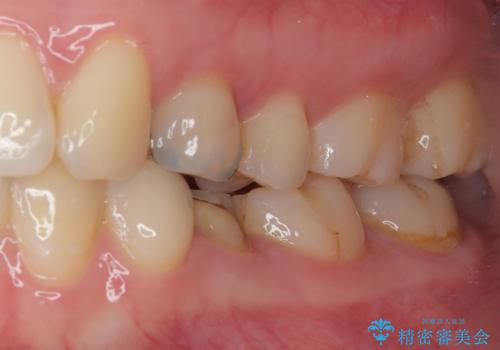

適合の良い被せものが入り、審美面も気に入っていただけました。被せものが割れていたという経緯もあったため少しだけ被せものの厚みを多めに確保してあります。

当院で矯正治療も行っているため、今後もリテーナーを使ってもらいながら経過を観察していきます。